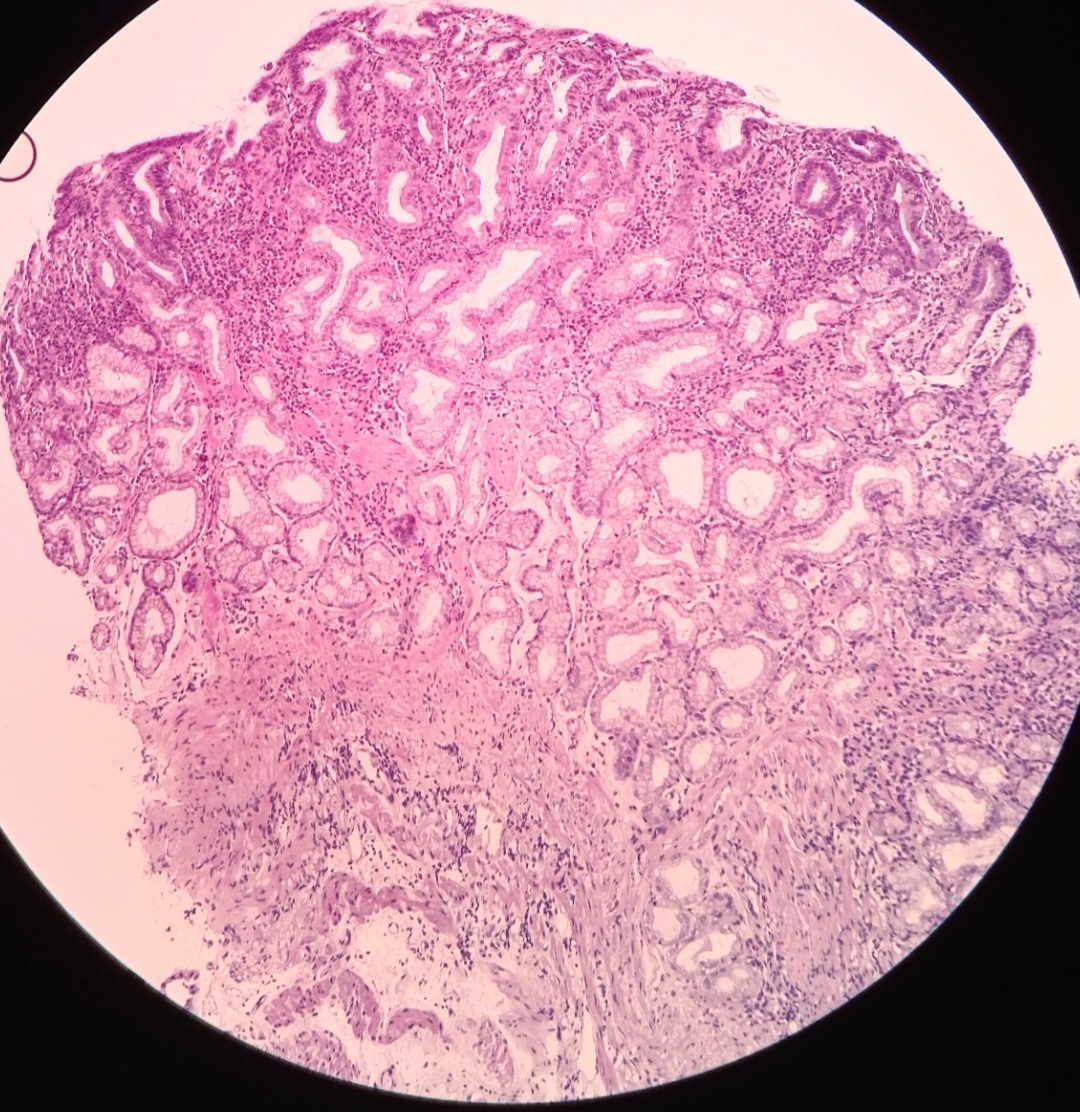

56床陈友文 胃窦腺癌 术前讨论

图片尺寸1000x1334